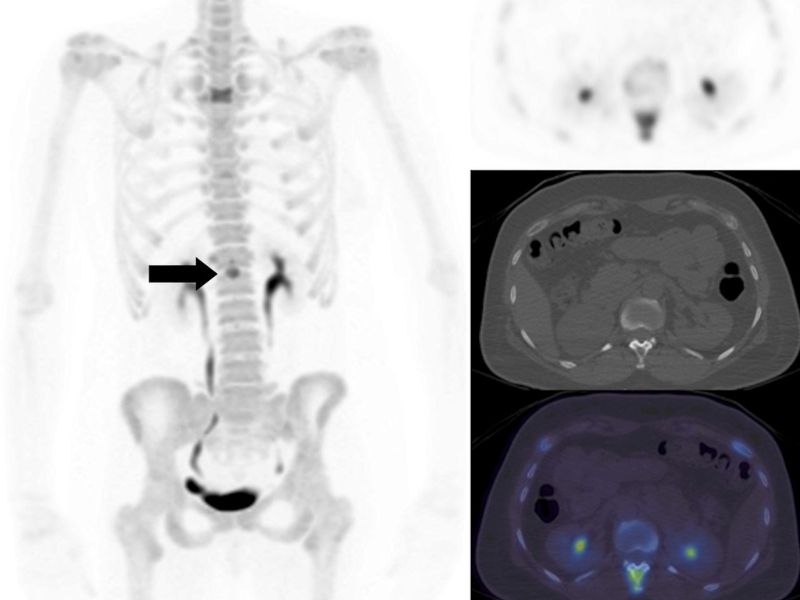

Chẩn đoán hình ảnh:

- Chụp xạ hình xương: Kỹ thuật này cho độ nhạy cao, có khả năng thăm dò toàn bộ hệ xương để phát hiện ung thư di căn sớm ngay cả khi chưa có triệu chứng lâm sàng. Ngoài ra, chụp xạ hình xương cũng giúp đánh giá đáp ứng điều trị trong quá trình theo dõi bệnh.

Chẩn đoán ung thư vú di căn xương